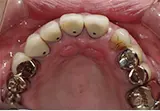

| 年齢/性別 | 60代女性 |

| 主訴 | 前歯が前に出てきた |

| 治療内容 | 全体的に歯周病やむし歯、根の治療(ヘミセクション)を実施。右上の歯にはサイナスリフト術を行い、骨の回復を待った後、半年後に2本のインプラントを埋入しました。 |

| 治療期間 | 9か月 |

| 費用 | 1,298,000円税込 |

| リスク・副作用 | 炎症反応によって術後に腫れや副鼻腔炎が生じることがあります。その程度は、手術の範囲や方法によって異なりますが、多くの場合、時間の経過とともに徐々に治まります。

ごく稀に、下顎奥歯の外科手術後に、唇や顎に痺れを感じることがあります。 |